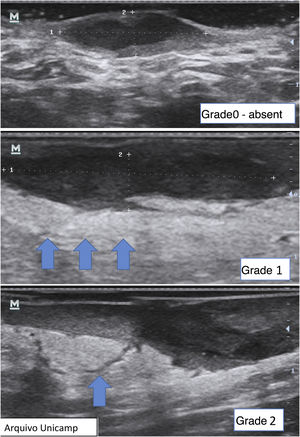

Another important complementary assessment is the grading of fibrosis (Fig. 11),16 which may appear as absent (grade 0), as a thin peripheral hypoechoic band with a fibrillar pattern (grade 1) or as a thick, peripheral hypoechoic band with a fibrillar pattern that invades the fistula lumen and produces a hypoechoic halo that is transversely visible (grade 2).

A fistula with a high degree of fibrosis is chronic and requires surgical treatment.

Finally, it is also possible to observe and grade perilesional edema, which directly correlates with inflammation and associated symptoms such as pain (Fig. 12).22,24 It may be absent (grade 0), show hypodermic hyperechogenicity (grade 1) or hypodermic hyperechogenicity and anechoic fluid among the hypodermal adipose lobes (grade 2).